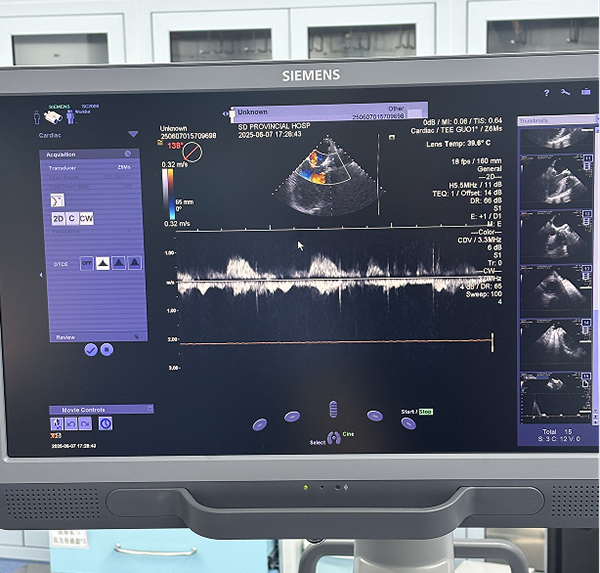

因患者主动脉瓣重度钙化,手术过程中存在栓子脱落造成脑梗的风险。麻醉团队在术中通过脑氧饱和度监测技术实时监测患者脑组织氧合情况,及时发现并纠正可能影响脑氧供的因素,最大限度地保护了患者脑功能,降低了术后神经系统并发症的风险。在冠脉支架植入和主动脉瓣膜置换过程中,采用的经食道超声心动图技术(TEE)实时监测心脏血流动力学变化,动态地观察心脏结构和功能,为手术团队提供精准的术中指导,确保了手术操作的精准性和安全性。

术中瓣膜置换完成后,

术中实时经食道超声心动图监测